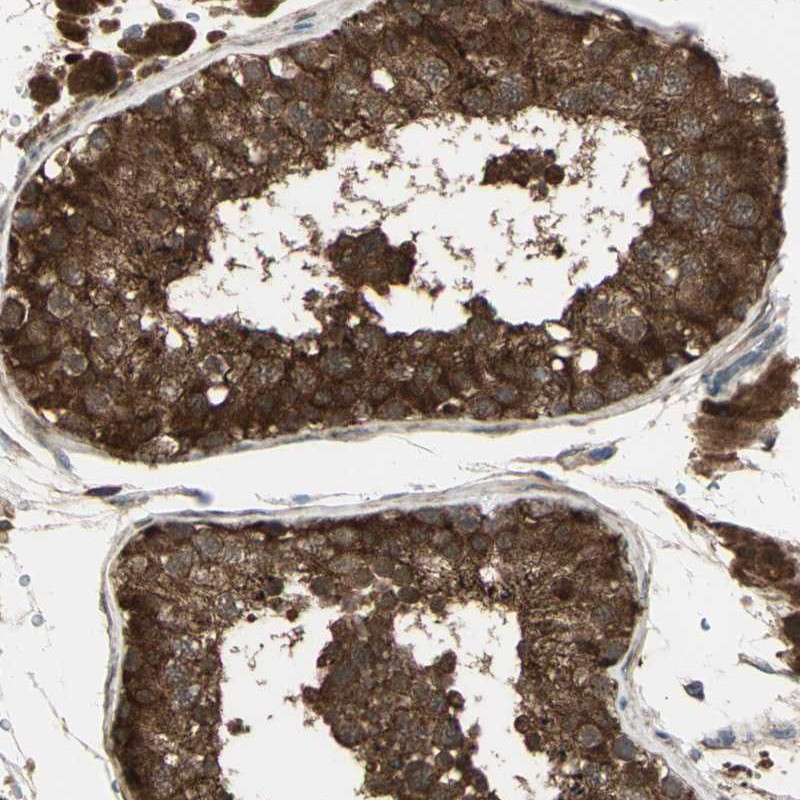

Immunohistochemical staining of human testis shows strong cytoplasmic positivity in cells of seminiferus ducts.